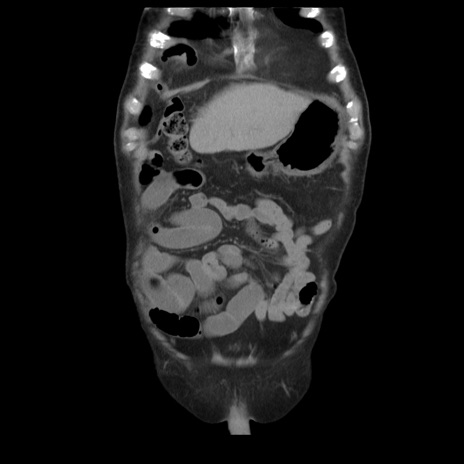

症例21(冠状断像)

【症例】70歳代男性

【主訴】腹痛

【現病歴】肝硬変・肝細胞癌にてかかりつけの方。約9時間前に食後より腹痛出現。症状が徐々に増悪し、嘔吐出現したため来院。

【既往歴】肝硬変、肝細胞癌(RFA、TACE後)

【身体所見】意識清明、表情苦悶様、BT 36℃、BP 129/78mmHg、P 88bpm、SpO2 97%(RA)、右上腹部から心窩部にかけて圧痛あり、反跳痛なし、筋性防御あり。

【データ】WBC 5800、CRP 0.16